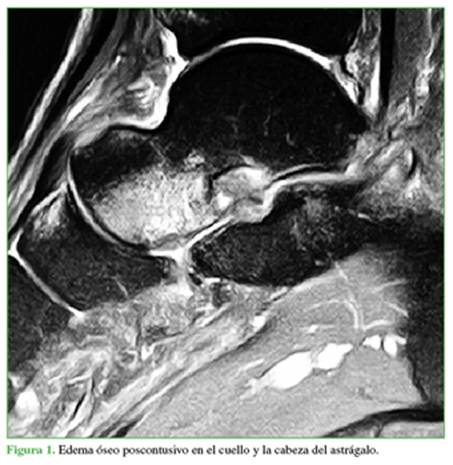

Un análisis de la bibliografía revela una discusión controvertida sobre el hallazgo del edema óseo en la RM observado en los sitios de inserción de los ligamentos laterales del tobillo (LPAA, LPC, LPAP), y su papel como indicador diagnóstico adicional para iniciar un tratamiento apropiado de esguinces agudos de tobillo (Figura 1). Asimismo, se debe prestar atención a los falsos negativos en las RM; sin embargo, si se presenta un edema óseo, esto debe considerarse como una bandera roja que indica atenuación del LPAA y el LPC.6

La localización más frecuente del edema óseo fue la cabeza y el cuello del astrágalo (32 pacientes, 64%), comúnmente cuando la RM mostró una lesión lateral o medial (15 casos, 30%). La segunda localización más común fue el cuerpo del astrágalo (20 pacientes, 40%) (Figura 2).